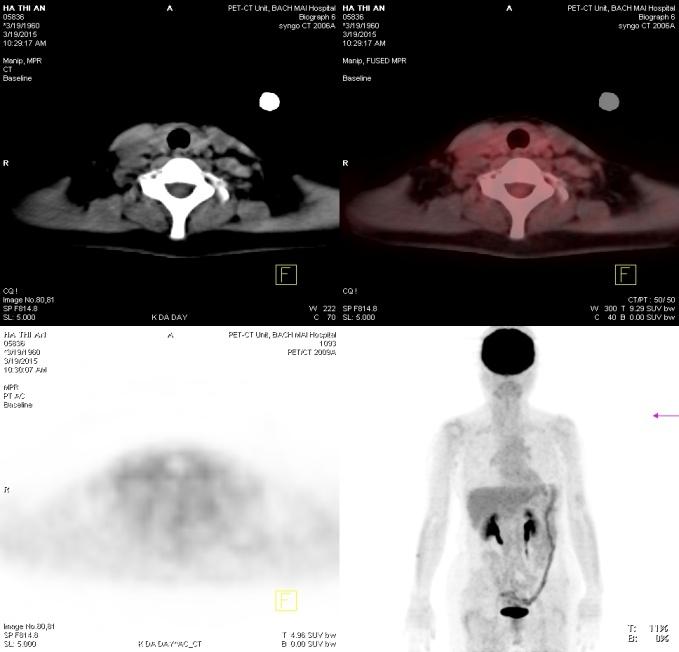

Chụp PET/CT đánh giá lại: Thành dạ dày tăng hấp thu 18F-FDG nhẹ, sỏi đường mật ngoài gan, tổn thương vùng cổ xương đùi phải không tăng hấp thu 18F-FDG. Không thấy hình ảnh tăng hấp thu và chuyển hóa 18F-FDG bất thường tại các vị trí khác trong cơ thể.

Trước điều trị: Hình ảnh hạch vùng thượng đòn trái trước điều trị (mũi tên đỏ)

Sau điều trị: Hình ảnh hạch vùng thượng đòn sau điều trị 3 chu kì hóa chất: hạch thượng đòn trái đã tan biến (mũi tên xanh: không còn tổn thương)

Hình 8: Hình ảnh so sánh trước và sau điều trị 3 chu kì hóa chất

Trước điều trị:Hình ảnh hạch ổ bụng trước điều trị 3 chu kì hóa chất

Sau điều trị: Hình ảnh hạch ổ bụng sau điều trị 3 chu kì hóa chất: Hạch ổ bụng đã tan hết. (Mũi tên xanh: không còn tổn thương)

Hình 9: Hình ảnh so sánh trước và sau điều trị 3 chu kì hóa chất

Trước điều trị: Hình ảnh tổn thương tại cổ xương đùi phải trước điều trị hóa chất (mũi tên đỏ)

Sau điều trị: Hình ảnh tổn thương tại cổ xương đùi phải sau điều trị hóa chất: Không tăng hấp thu FDG (mũi tên xanh)

Hình 10: Hình ảnh so sánh trước và sau điều trị 3 chu kì hóa chất

Chụp PET/CT: Không thấy hình ảnh tăng hấp thu và chuyển hóa bất thường 18F-FDG trong cơ thể.

Hình 12: Không thấy hình ảnh tăng hấp thu 18F-FDG tại vùng hạch thượng đòn 2 bên.

Hình 13: Không thấy hình ảnh tăng hấp thu 18F-FDG tại hạch ổ bụng.

Hình 14: Không thấy hình ảnh tăng hấp thu 18F-FDG tại vùng cổ xương đùi phải.